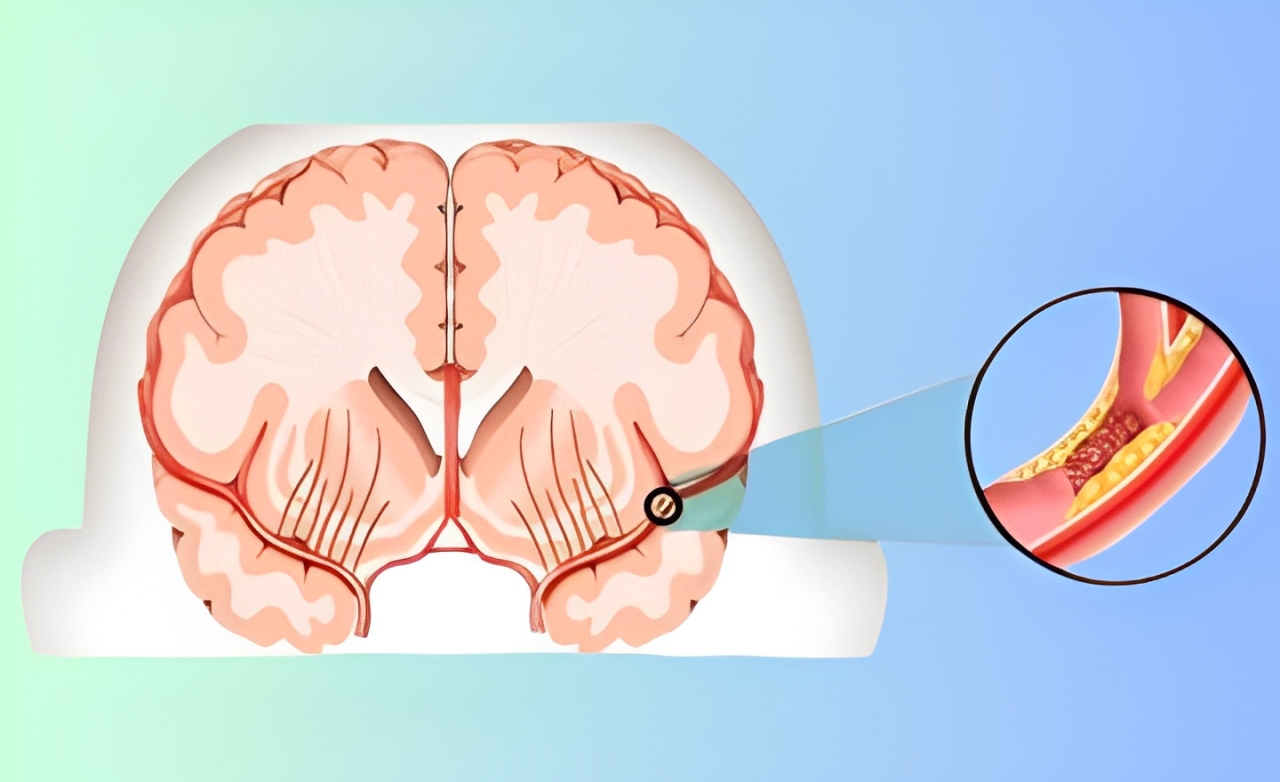

Narrowing of the carotid arteries due to plaque buildup, reducing brain blood flow and increasing risk of transient ischemic attacks.